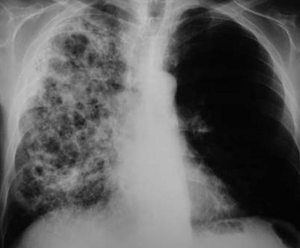

- CXR may show:

- Upper lobe infiltrates

- Fibrosis, scarring

- Cavitations

- Diffuse interstitial or reticulonodular lung infiltrates

- CXR

- Pneumonitis with hilar adenopathy

- Focal pulmonary infiltrates with light exposure

- Diffuse infiltrates with heavy exposure